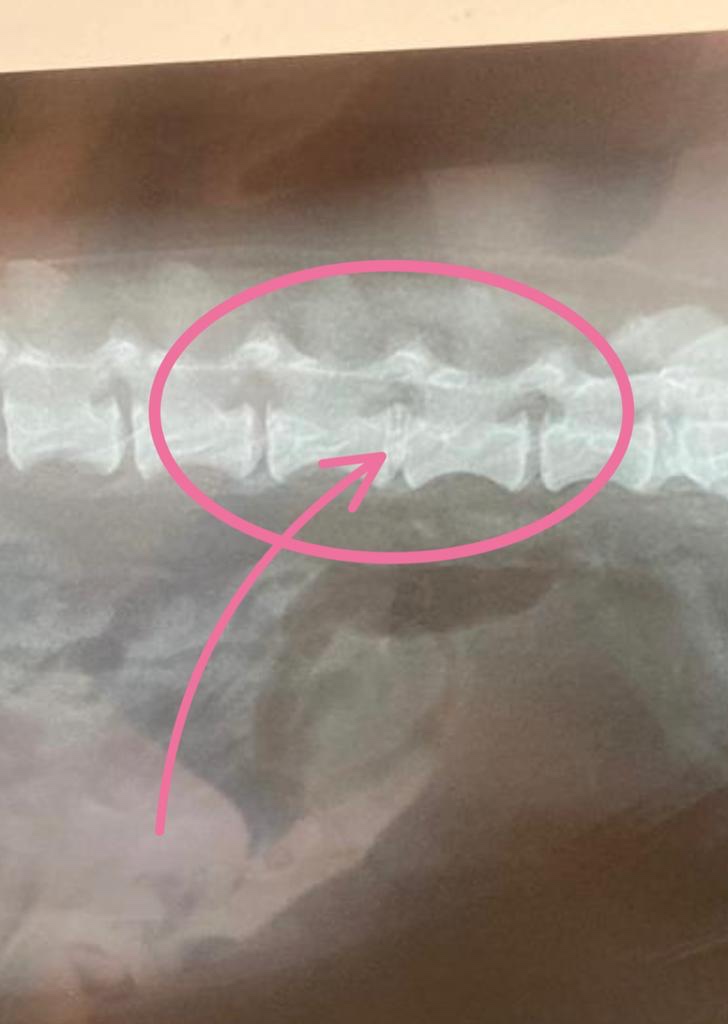

寵物主人實證分享:我家狗仔叫榛榛,在一個月前突然行唔到路,又連續幾日都唔食嘢,後來帶去睇獸醫,經照X光片後發現佢第五和第六節脊骨之間有問題,但醫生當時都未確定係咩問題,又或者需要做手術。

獸醫當時初步估計是腰椎盤凸出,要照磁力共震,先可以知道問題所在的位置,腰椎盤凸出分為5級,由第一級是只感覺到痛,去到第5級四肢無力,去大小便都有問題,按當時情況,榛榛是第三級,後腿無力。獸醫就說如果是腰椎問題最好盡快去照,因為會惡化得好快。收費狗仔磁力共振大約9千左右,未包麻醉藥⋯⋯